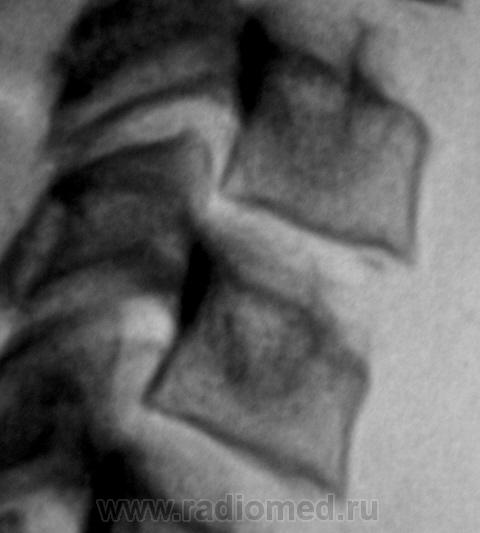

Ребёнок 1о лет.  Произведена рентгенография шейного отдела позвоночника.

Просьба высказать мнение по поводу представленных изображений.

Мы, очень редко сталкиваемся с "детской патологией". Этот случай, конечно, не понятен, да и не понятен он мне, даже после Вашего коммента. Ведь "ступенька" дифференцируется изолировано только по передне-верхнему краю С5. В других позвонках "такого" нет, и все одно "это" считается нормой?

Да, и нижняя замыкательная пластика С4, на мой взгляд, отличается от других нижних замыкательных пластинок тел позвонков, которые "ровные" и четкие. Субъективно, на мой взгляд, патология в сегменте С4-С5 имеется.

Вероятнее всего это что-то связанное с апофизом, возможно, своеобразная остеохондропатия типа Ш.-Мау.

Поддерживаю норму. Хотя нужно заглянуть в рентгенанатомию, и посмотреть сроки ассимиляции апофизов...

Моё мнение - что это вариант развития апофизов, на данный момент не играющий клинического значения.

Аномалия развития - бабочковидный позвонок С5.